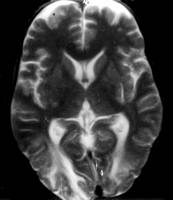

Modificari precoce in boala sunt cosiderate aparitia zonelor de hipersemnal, definitorii, pe imaginile cu predominanta T2 (fig. 2), cu precadere la nivelul substantei albe subcorticale occipitale mai mult decat a celei frontale. In majoritatea cazurilor, substanta cenusie este integra, chiar si in cazurile avansate.

Figura 2: imagine prin rezonanta magnetica avand

predominanta T2, prezentand demielinizare difuza a

substantei albe, la un baiat in varsta de 8 ani, cu PESS.

Figura 3: imagine prin rezonanta magnetica avand

predominanta T2, prezentand zone hiperintense in ambele

regiuni occipitale.